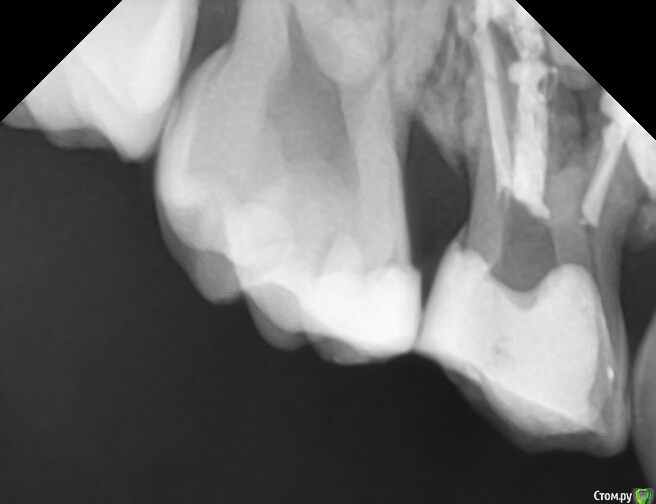

CRAZYDUCK Опубликовано 22 апреля, 2016 Поделиться Опубликовано 22 апреля, 2016 (изменено) 54 зуб ,в начале -лечение пульпита ампутацией ,через 1,5 года приехала со свищем в проекции щечного корня, без жалоб на это зуб ,сама увидела свищ .помыла гипохлоритом ,метапексом запломбировала ,килограмм метапекса из свища вышел.Через три месяца свища нет , но из канала ,в котором был свищ метапекс рассосался Надежнее удалять сомнительные ,с резорбцией ,большими очагами разрежения .это мое мнение Изменено 22 апреля, 2016 пользователем CRAZYDUCK 1 Ссылка на комментарий

crown Опубликовано 23 апреля, 2016 Автор Поделиться Опубликовано 23 апреля, 2016 2016-04-22 21.19.34.jpg54 зуб ,в начале -лечение пульпита ампутацией ,через 1,5 года приехала со свищем в проекции щечного корня, без жалоб на это зуб ,сама увидела свищ .помыла гипохлоритом ,метапексом запломбировала ,килограмм метапекса из свища вышел.2016-04-22 21.19.34.jpgЧерез три месяца свища нет , но из канала ,в котором был свищ метапекс рассосался 2016-04-22 21.19.00.jpgНадежнее удалять сомнительные ,с резорбцией ,большими очагами разрежения .это мое мнение я думаю причина в метапексе, он слишком быстро вымылся из разбитого апекса и опять резорбция, наверное в этой ситуации спас бы цинкэвгенольный цемент Ссылка на комментарий

CRAZYDUCK Опубликовано 23 апреля, 2016 Поделиться Опубликовано 23 апреля, 2016 (изменено) я думаю причина в метапексе, он слишком быстро вымылся из разбитого апекса и опять резорбция, наверное в этой ситуации спас бы цинкэвгенольный цементЯ останусь при своем ,просто этот зуб изначально подлежал удалению .Сегодня посетила семинар Елены Владимировна Небольсиной .Масса позитивных эмоций !настолько открытый ,позитивный и терпеливый человек .Елена приехала работать ! У нас был насыщенный день ,было 2 или 3 небольших 15 минутных перерывов. День полностью был посвящен обучению !Насчет ЦОЭ -в дентал фентэзи перестали им работать именно в каналах ,так как он ПРАКТИЧЕСКИ не рассасывается! Я не спросила название ,так как ЦОЭ (Эодент )просто стоит у меня без работы.но было очень много фото и рентген снимков ,подтверждающих, что рассасывание не происходило . Изменено 23 апреля, 2016 пользователем CRAZYDUCK 3 Ссылка на комментарий

Kota Опубликовано 24 апреля, 2016 Поделиться Опубликовано 24 апреля, 2016 Я останусь при своем ,просто этот зуб изначально подлежал удалению .Сегодня посетила семинар Елены Владимировна Небольсиной .Масса позитивных эмоций !настолько открытый ,позитивный и терпеливый человек .Елена приехала работать ! У нас был насыщенный день ,было 2 или 3 небольших 15 минутных перерывов. День полностью был посвящен обучению !Насчет ЦОЭ -в дентал фентэзи перестали им работать именно в каналах ,так как он ПРАКТИЧЕСКИ не рассасывается! Я не спросила название ,так как ЦОЭ (Эодент )просто стоит у меня без работы.но было очень много фото и рентген снимков ,подтверждающих, что рассасывание не происходило . здесь соглашусь. у меня немного опыта эндодонтического лечения, но если и пломбировала каналы, то только ЦОЭ, так как я заканчивала институт 15 лет назад и там даже кальций рекомендовали менять на ЦОЭ. так вот, он действительно почти не рассасывается. когда приходит время смены, то дает обострение, плюс мне не нравится то, что затягивает таким образом естественную резорбцию и физ.смену зуба. а пломбировка кальцием как то не вкладывается в мою картинку ) пока... но нужно пробовать и видеть свои результаты. 1 Ссылка на комментарий